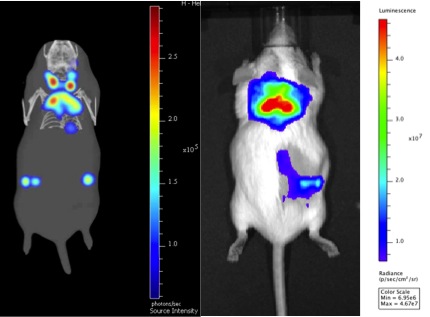

In vivo optical imaging is a molecular imaging technology that uses light-emitting agents to visualize and measure physiological and/or biological processes within small live laboratory animals such as mice and rats. Drug candidates, cells or biomarkers are labeled with a light emitting compound (a "reporter") that generates photons – fluorescence or bioluminescence.

The system is equipped with specific excitation and emission filters between 430 and 850 nm. These allow separating the signal from different fluorescent or bioluminescent sources within an animal (Spectral Unmixing). Moreover, our system is equipped with a multi-modal bed allowing the co-registration of bioluminescence/fluorescence images with CT images. Finally, thanks to specific algorithms, 3D reconstruction is also possible!